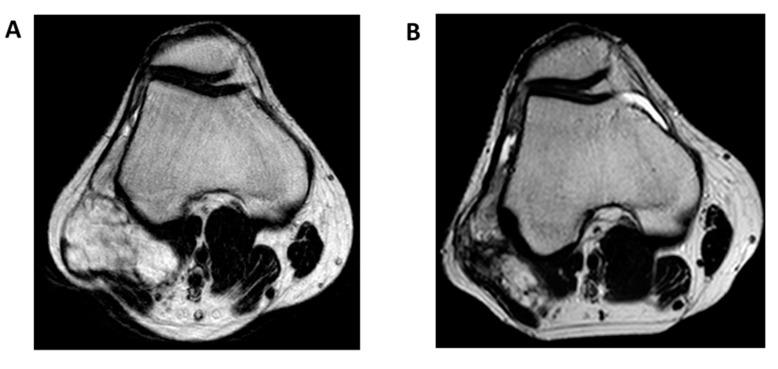

骨外黏液样软骨肉瘤(EMC)是一种极为罕见的间叶性肿瘤,其分化情况尚不明确,主要发生于近端肢体和肢带的深部软组织。EMC的特征是涉及 基因的易位,该基因可与不同伙伴基因进行读码框内融合,最常见的伙伴基因是 或 。尽管EMC的生物学特性仍未明确界定,但最近的研究已开始揭示NR4A3嵌合蛋白对EMC发病机制和临床结局的具体作用。局限性疾病的标准治疗方法是手术,联合或不联合放射治疗,即使复发风险约为50%,预期生存期仍会延长。在晚期病例中,除了目前用于软组织肉瘤的标准化疗外,抗血管生成药物最近已显示出有前景的活性。本综述的目的是提供局限性和晚期疾病的治疗现状,重点关注EMC可用的药物治疗。还将讨论当前研究的生物学基础和未来展望。

https://cdn.ncbi.nlm.nih.gov/pmc/blobs/9482/7563993/ac637fffbb0c/cancers-12-02703-g003.jpg

https://cdn.ncbi.nlm.nih.gov/pmc/blobs/9482/7563993/94cd7d84d9e8/cancers-12-02703-g001a.jpg

https://cdn.ncbi.nlm.nih.gov/pmc/blobs/9482/7563993/13b259b5ddc5/cancers-12-02703-g002.jpg